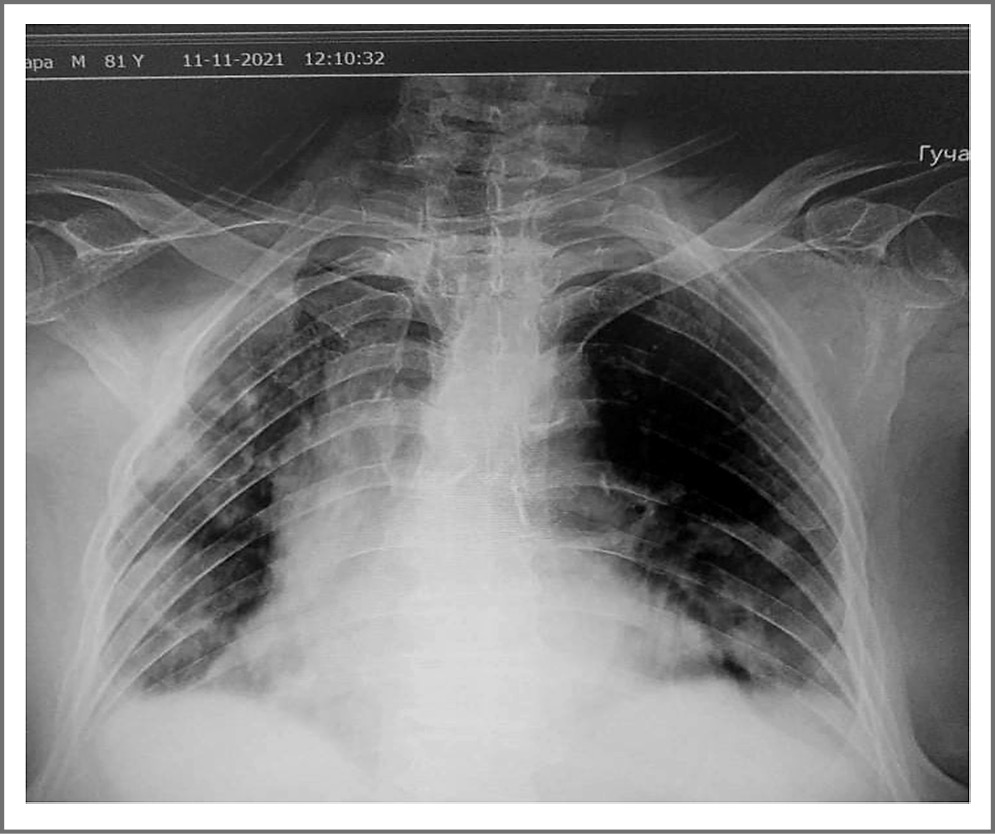

В стационаре неоднократно проводилось рентгенологическое исследование легких. На рентгенограмме ОГК от 11.11.2021 (рис. 1) до введения тоцилизумаба определяется двустороннее диффузное снижение пневматизации. Корни легких прикрыты тенью сердца. Купола диафрагмы расположены обычно. Синусы завуалированы. Границы сердца сохранны. Срединная тень не смещена. Заключение: двусторонняя пневмония, КТ-3.

Рис. 1. Рентгенограмма ОГК больной Ж. от 11.11.2021. / Fig. 1. Radiograph of chest organs patient Zh. from 11.11.2021.